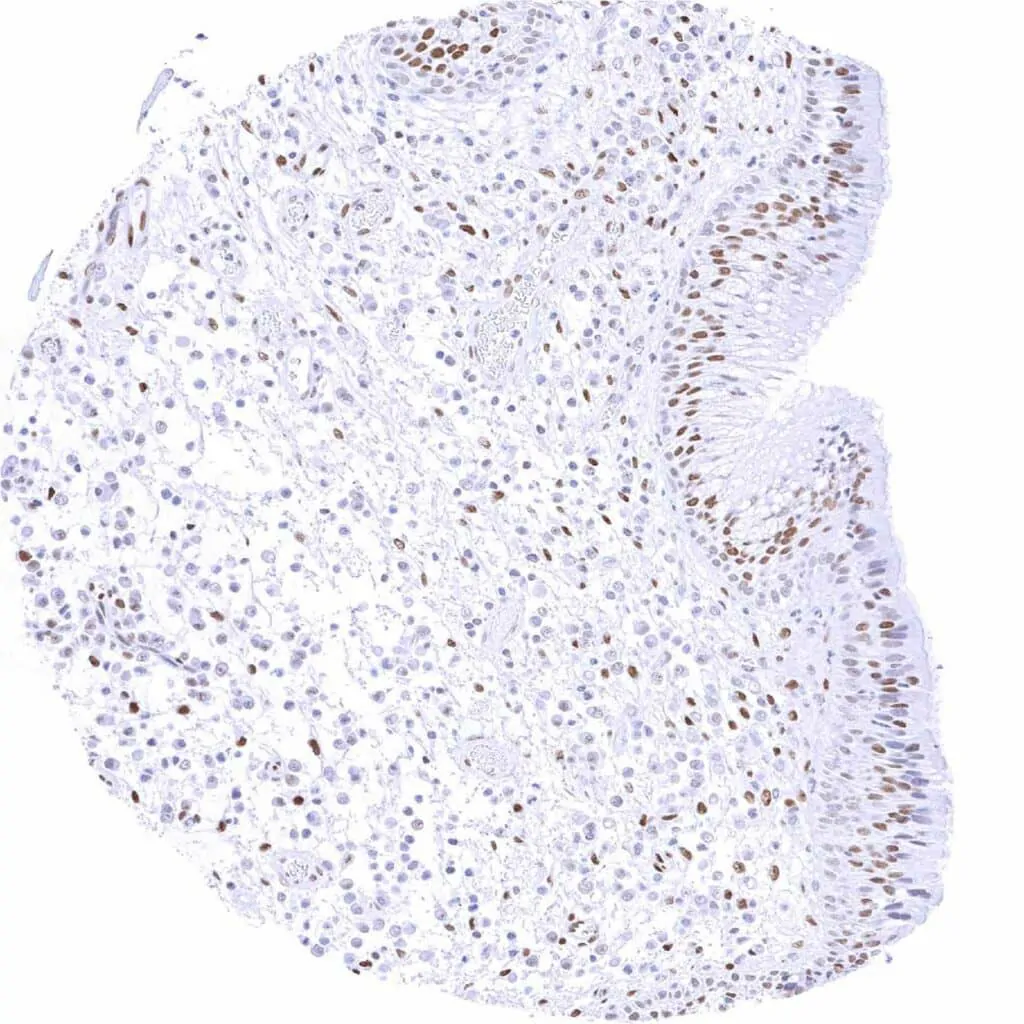

Testis – Moderate to strong TLE1 staining of spermatogonia